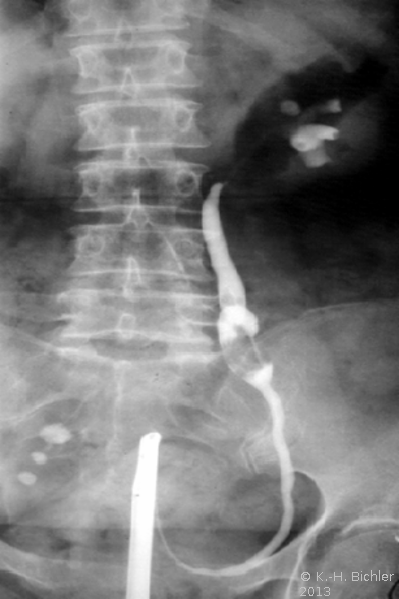

- Abbildung: Ureterabgangsstenose links bei 15jährigem Mädchen

- a) Retrograde Sondierung links: Ureterabgangsstenose präoperativ

- b) Retrograde Sondierung postoperativ